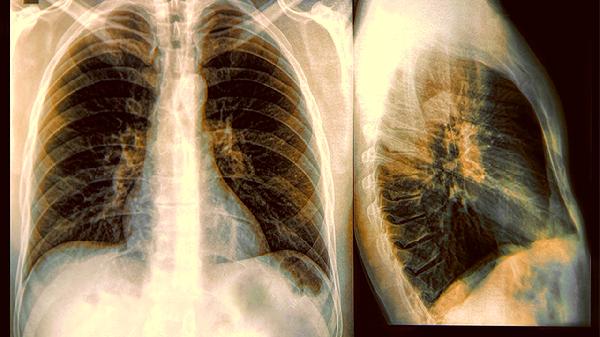

1.影像学升级

普通胸片可能漏诊早期病变,低剂量CT能发现小至2mm的结节,辐射量仅相当于乘坐两小时飞机。高危人群每年一次,检出率可提升74%。